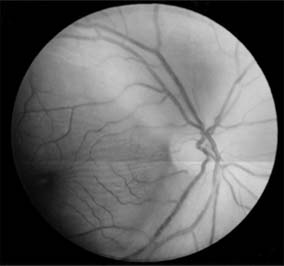

Figure 14-11

Figure 14-11: Retinal nerve fiber layer in demyelinating optic neuropathy of multiple sclerosis. The upper temporal nerve fiber bundles show multiple slit-like areas of thinning (arrows) representing retrograde axonal atrophy from subclinical disease in the optic nerve. Vision in the eye was 20/20.